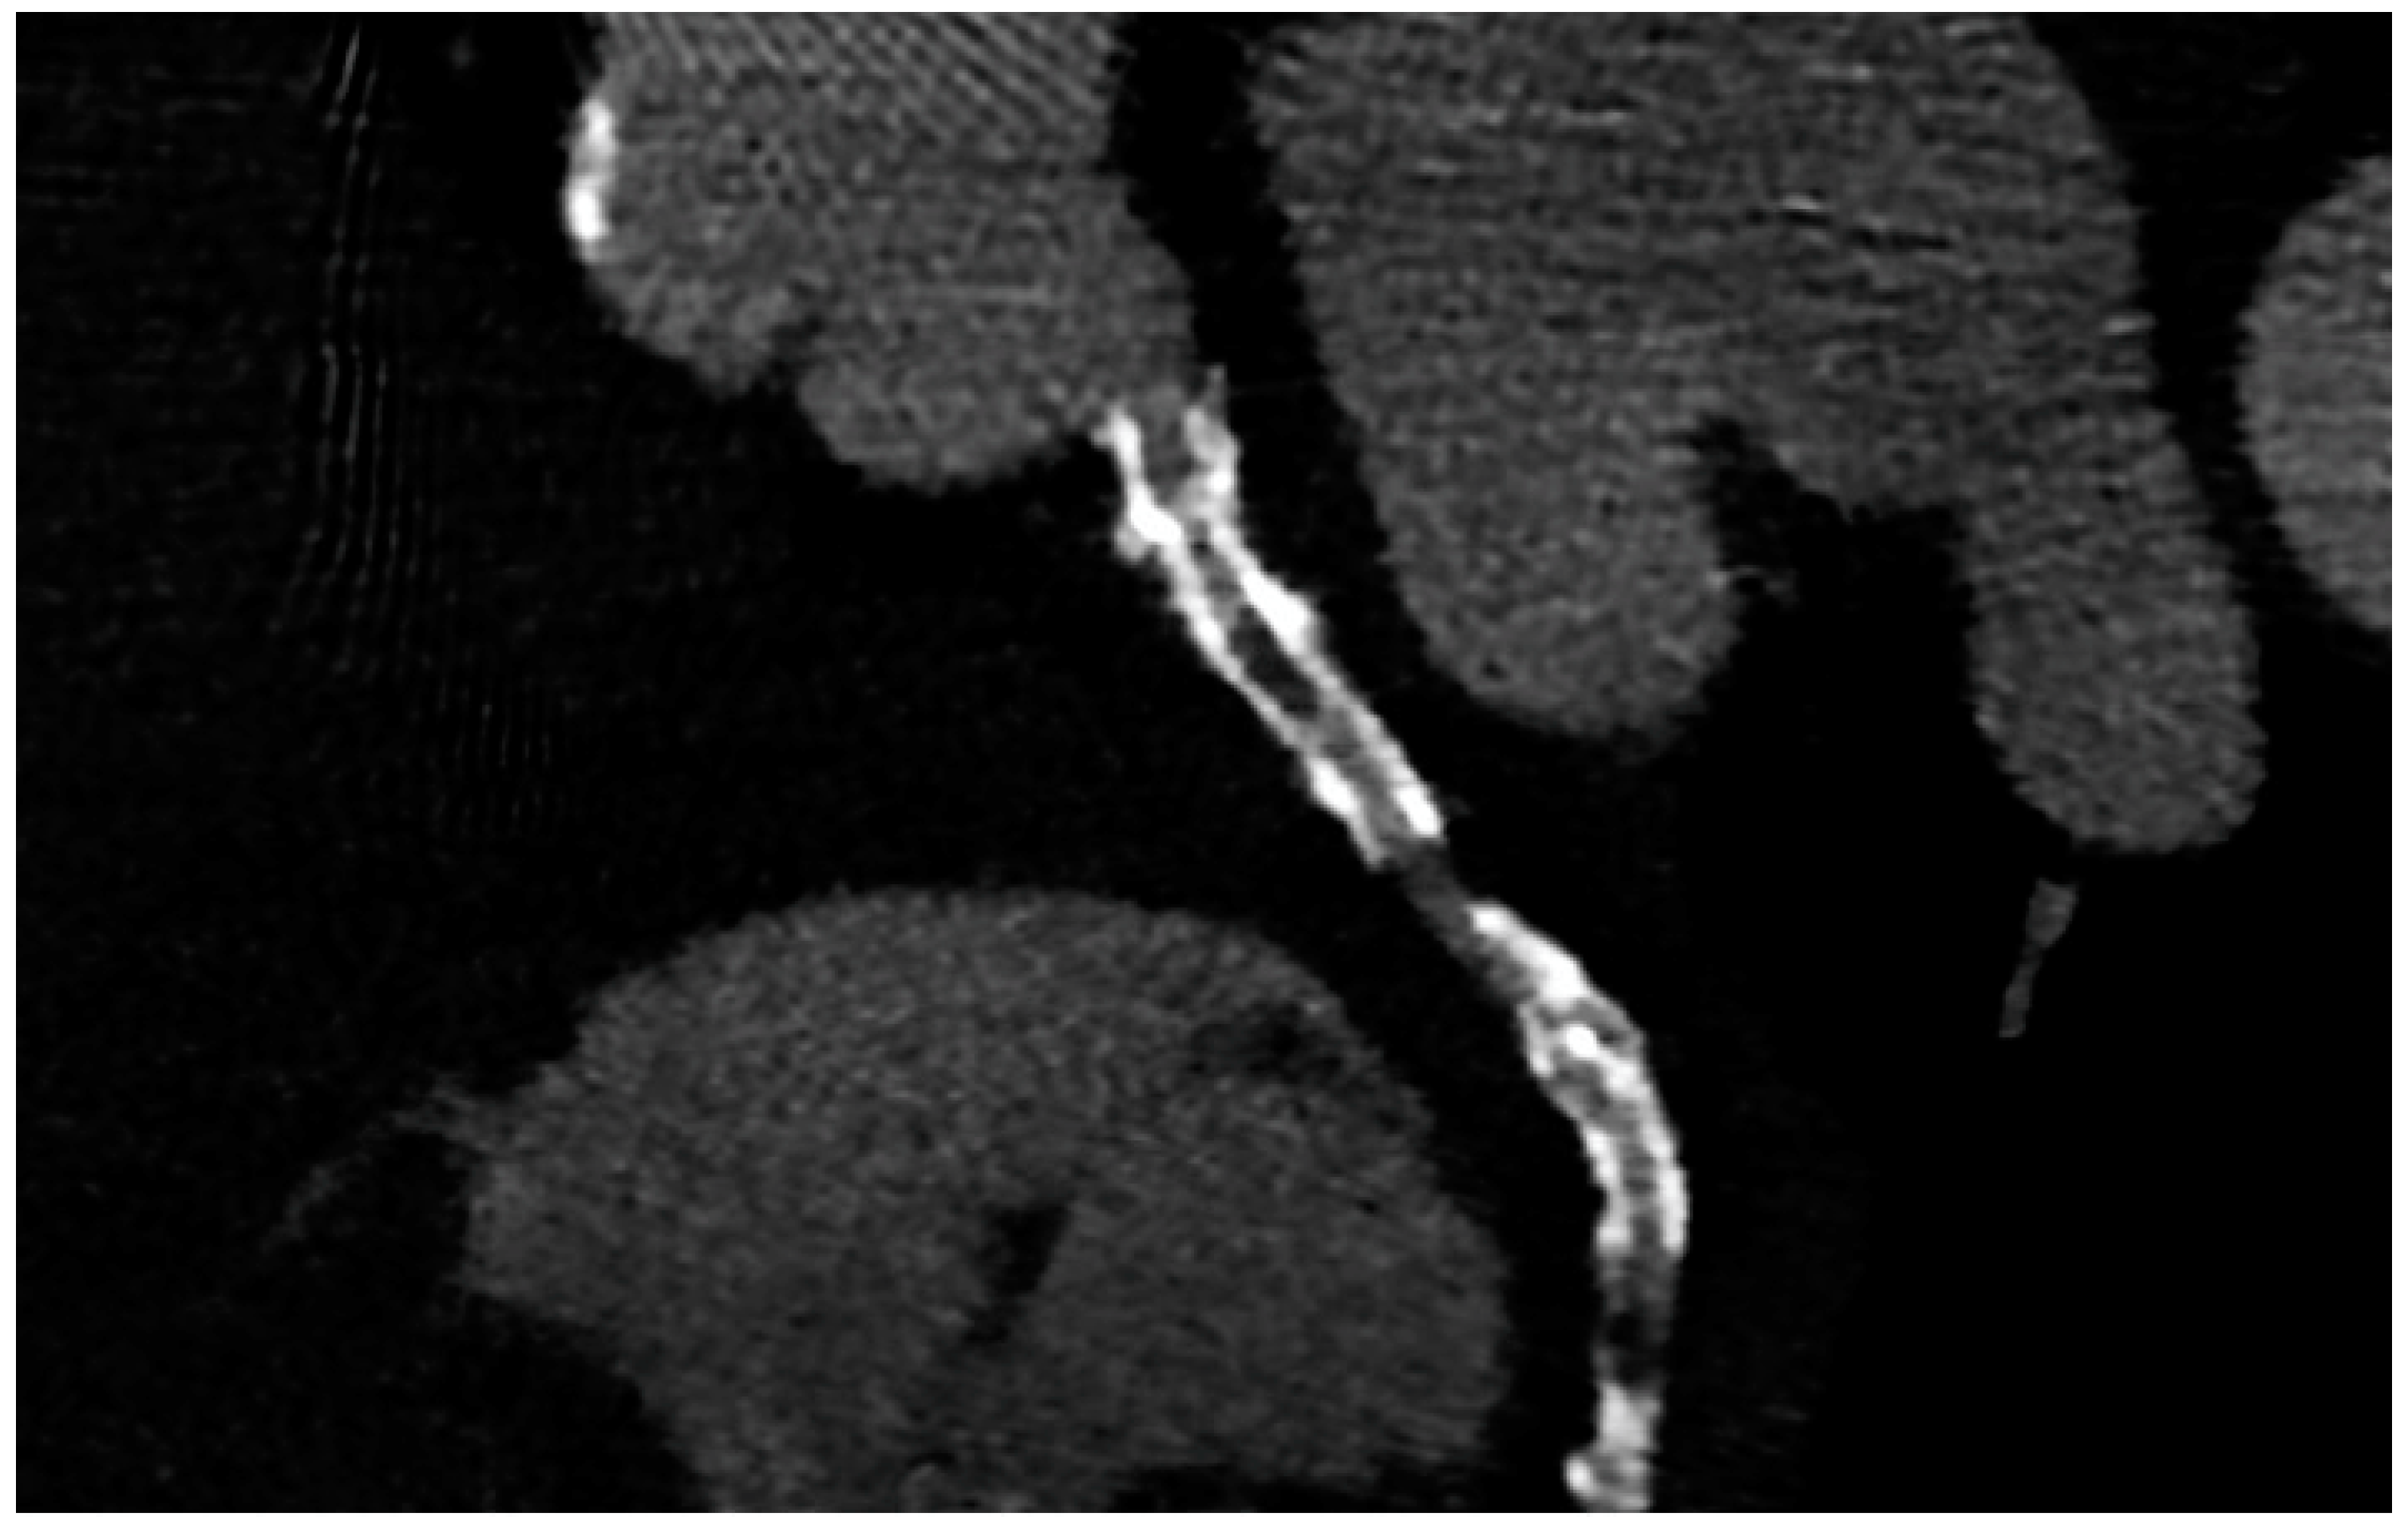

PCI of the left main (LM) improves survival, and in most cases, it is not inferior to surgical revascularization [14]. Intra-stent restenosis (ISR) is a complication of paramount importance, especially in the setting of LM revascularization, because of its relationship to adverse events. With current stents, ISR is due to neo-atherogenesis, which leads to a higher risk of destabilization and stent thrombosis. In the setting of LM, ISR at 15-month follow-up has been revealed to be present in up to 16% of total subjects, requiring invasive revascularization in 7% of cases. Coronary angiography represents the best technique for ISR assessment [14]. Planned Angiography Control (PAC) has been proposed to diagnose and treat ISR promptly, but its benefit remains to be established. An increased rate of percutaneous coronary interventions (PCI) without a reduction in cardiovascular events has been mainly reported. Some technical issues about the use of CCTA in coronary stent imaging have been described, such as the blooming effect, partial volume effect, motion artifacts, and inadequate intravascular contrast enhancement. The blooming effect is the most important issue, corresponding to a phenomenon in which stent struts appear thicker, causing an underestimation of stent lumen. However, with new technology development, CCTA provides a precise, noninvasive reconstruction of the coronary tree and may offer an alternative to invasive coronary angiography [15]. Figure 1 shows three multiplanar reconstructions of LM and left anterior descending with a drug-eluting stent previously implanted: struts of the stent appear clearly detectable, the stent seems to be well-positioned, and regarding stent lumen, it can be noted that there is good opacification and no evidence of ISR. Medium and distal tracts of the left anterior descending seem to be free from plaque proliferation and/or stenosis. Figure 2, instead, shows an ISR of a stent implanted in the proximal segment of the left circumflex coronary artery. Therefore, Figure 1 and Figure 2 demonstrate the feasibility of LM and proximal segment stent assessment by CCTA. Its use in the PAC setting has been investigated and may provide relevant advantages as it is a noninvasive examination. There are three different methods to determine the degree of ISR with CCTA: qualitative, semi-quantitative, and quantitative. The first technique provides that significant ISR (reduction of luminal diameter >50%) is visually detected: ISR is identified as a hypodense layer between the struts and the lumen. The second method is characterized by a four-point scale where 1 corresponds to the patency of the stent and 4 results in stent occlusion. Finally, the third technique provides that the percentage of stenosis is calculated as the ratio between diameters in the short axis of the narrowest stent lumen and of the proximal and distal reference segments [15]. Roura G et al. evaluated the agreement between CCTA and intravascular ultrasound (IVUS) to assess in-stent lumen diameters and lumen area of LM stents: the study highlighted a good agreement between the two techniques so that CCTA can be considered to analyze LM ISR [4]. A study by Van Mieghem CAG et al. assessed the performance of CCTA in the analysis of LM stenting: they enrolled 74 patients scheduled for follow-up coronary angiography after LM stenting, and they performed CCTA before coronary angiography. The study demonstrated that the accuracy of CCTA for detecting LM ISR was 98%; in particular, diagnostic accuracy was 98% both for patients with stented LM and with distal LM bifurcation lesions and only one side branch treated [5]. In subjects with complex bifurcation stenting (i.e., LM and both major side branches), the reliability of CCTA was 83%. The low number of false-positive scans leading to unnecessary diagnostic coronary angiograms should be acceptable, taking into account the potentially serious consequences of LM ISR [5]. Furthermore, the study underlined that the evaluation of stent diameter and area by CCTA had a good correlation with IVUS assessment. One of the most important issues arising from this study was the high radiation dose required for the analysis of stents by CCTA. However, as previously reported, new scanner developments (i.e., dual-source CT scanners) reduced patient dose.

Figure 2.

ISR in a stent previously implanted in the proximal segment of the left circumflex artery.